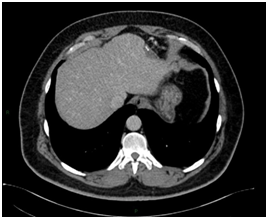

Intrahepatic splenosis shows increased enhancement on CT or MR images during the arterial phase. Performing gadoxetic acid–enhanced hepatocyte-phase MR imaging does not help because intrahepatic splenosis is hypointense during the hepatospecific phase. The MR technique involving administration of small iron oxide particles (SPIO-Endorem), which is taken up by liver and spleen reticuloendothelial cells, has proven to be effective in differentiating intra-hepatic splenosis from other lesions.14,15,18 With SPIO (superparamagnetic iron oxide) intrahepatic splenic nodes remain hyperintense.19 Noncontrast CT reveals a well circumscribed iso- or hypodense mass in the liver, while noncontrast MRI demonstrates mild-to-moderate hyperintensity on T2-weighted image and hypointensity on the T1-weighted image. A dynamic study on CT and MRI shows a slight to intense enhancement, which may be homogeneous or heterogeneous during the arterial phase but enhancement is diversely during the portal venous and equilibrium phases in different cases. Compared with the surrounding hepatic parenchyma, the lesion could reveal hypodensity and hypointensity, or hyperdensity in the arterial phase. Or it can demonstrate diminished enhancement, slight enhancement, or increased enhancement during the following phases (Figure 2 & 3).19,20

Figure 3Postoperative figures A, B, C, D and E. Computed Tomography (CT). Postoperative CT in the axial plane in the post-contrast venous phase show signs of partial resection of the liver segment II (A,B, C and D), as well as splenectomy with small implants of splenic tissue in the left subphrenic region (E).